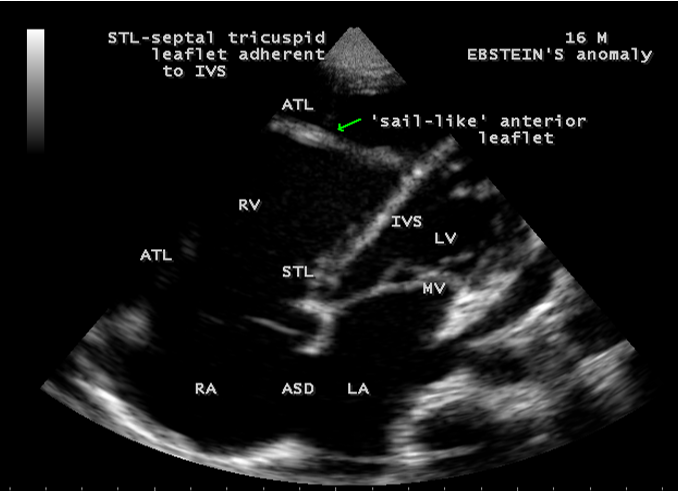

Case 1 (16-year-old cyanotic male with Ebstein’s anomaly) A 16-year-old male presented with cyanosis and he had features of an atrial septal defect such as wide, fixed splitting of second heart sound at left second intercostal space and a grade 2/6 systolic murmur at the lower left sternal border. 2D echocardiography revealed the features of Ebstein’s anomaly such as tethering of septal tricuspid leaflet (STL) to the ventricular wall associated with an ostium secundum type atrial septal defect (ASD) and low mild tricuspid regurgitation jet as shown in Figures 1 to 3

Echocardiographic features Echocardiography is the diagnostic test of choice for Ebstein’s anomaly and the first echocardiographic diagnosis was reported by Lundstrom in 1969. The first diagnostic criteria for Ebstein’s anomaly using a multi-crystal two-dimensional system was defined by Hagan in 1974 [33] and they were able to recognize the apical displacement of the septal tricuspid leaflet and an elongated anterior tricuspid leaflet with increased excursion. The septal leaflet of the tricuspid valve attaches chiefly to the ventricular septum , but part of its basal attachment is to the posterior wall of the right ventricle [34] and it normally exhibits a slight but distinct apical displacement of its basal attachment to the central fibrous body compared to the mitral valve. The distal displacement of septal origin of tricuspid valve seems to be the best echocardiographic criterion as the characteristic sign for Ebstein’s anomaly and the degree of maximal displacement in normal hearts varies considerably with a mean difference of approximately 6 mm with mitral valve. To define the anatomic severity of Ebstein’s anomaly, four-chamber view is the best to demonstrate the apical displacement of septal tricuspid leaflet [35]. The ratio between the mitral-to-apex distance and the tricuspid-to-apex distance varies from 1 to 1.2 in normal subjects and 1.8 to 3.2 in patients and it is 3.6 as in Figure 18 with Ebstein’s anomaly. The true distance in the level of insertion of atrioventricular valves is obtained by substracting the tricuspid-to-apex distance from the mitral-to-apex distance with a mean value of 27.25 ± 12 mm in patients with proven Ebstein’s anomaly and it is 60 mm as shown in Figure 18 compared to reference group (5.7 ± 2 mm). Kambe and coworkers calculated the distance between both atrioventricular valves directly as a mean value of 21 mm with a range of 14 to 32 mm [36]. A maximum difference in the level of valve insertion of >15 mm in children and >20 mm in adults is discriminated between normal and Ebstein’s anomaly [37],[38]. Despite this fact, a patient with an ‘unequivocal’ Ebstein’s malformation can be encountered in whom the diagnosis cannot be made with certainity solely on the basis of apical displacement of the septal tricuspid valve leaflet. Occasionally, the leaflet attaches to the trabecular part rather than the inlet part of the septum, the conventional four-chamber view will not reveal any septal insertion as shown in Figures 28 and 29.

The anterior tricuspid leaflet is not involved in the process of downward displacement, it may be abnormally inserted occasionally and Shiina, et al documented the apical displacement of anterior tricuspid leaflet in 14% of cases echocardiographically [39]. The anterior leaflet forms a large, sail-like intracavitary curtain as in Figures 14, 25 and contains muscular strands instead of consisting entirely of a fibrous membrane as in the normal tricuspid valve [40]. It is potentially mobile with a brisk sail-like movement as shown in Figure 21 to 24 [41], free bloating with a ‘whipping motion’ across the right ventricular outflow tract (RVOT) as shown in Figure 26 and in some cases, the movement is restricted due to its adherence to the ventricular wall as in Figure 1 and 2, 4 and 9. It is often fenestrated, may in part be musculaized , inserting into the trabeculations of the right ventricle (RV) as in Figure 28 and rarely, the anterior leaflet forms an ‘atretic’ membrane that spans the midportion of the right ventricular cavity as in Figure 16.

The tricuspid orifice is typically incompetent as in Figures 3, 5 and 10, occasionally stenotic, and rarely imperforate as in Figure 16 [44],[45]. The true anatomic tricuspid annulus occupies its normal position at the right atrioventricular junction and it is less well defined than in a normal heart. The annulus tends to be appreciably dilated and contribute to the development of valvular incompetence. In extreme downward displacement of posterior and septal leaflets, the closure of the tricuspid annulus depends on the size and potential excursion of anterior leaflet. When the chordal attachments are short and the leaflets contain multiple or large fenestrations, adequate valve closure is impossible to achieve and varying degrees of regurgitation results. Color flow imaging and Doppler interrogation can establish the relatively low velocity regurgitant flow as in Figure 6, which begins at the level of the displaced septal and posterior leaflets as in Figures 5 and 10 and courses through the atrialized right ventricle into the right atrium proper as shown in Figure 5. Tricuspid regurgitation increases by annular dilatation [46]. During contraction of the atrium, the atrialized portion of the right ventricle balloons out and acts as a passive reservoir. Functional improvement of right ventricle depends on the severity of tricuspid regurgitation and on the ratio of the combined areas of right atrium and atrialized right ventricle relative to the areas of functional right ventricle and left ventricle [47]. Celermajer, et al described an echocardiographic grading score for neonates with Ebstein’s anomaly as shown in the Table 5 [48].